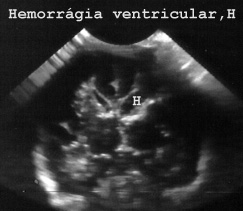

En cambio la ecografía permite hacer medidas in situ del tamaño de los ventrículos de la corteza y de las diversas estructuras además de las muestras que cogemos para estudio histológico. Por otra parte la rapidez con que pueden hacerse los estudios microscópicos hace que la ecográfia cerebral en los niños en el estudio postmortem de ecopsia o de autopsia sea muy conveniente. En la Fig 68 había una hemorragia en el ventrículo cerebral.

68HERRGV.JPG (17588 bytes)

Fig 68